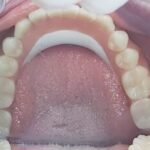

Patientenfall, zahnloser Unterkiefer. Komplett metallfreie Lösung. Der Zirkonium-Steg auf 4 Implantaten garantiert einen absolut festen Sitz, Sicherheit und Kaukomfort.

4 Implantate im Kinnbereich

Ein Zirkoniumsteg zur Befestigung des Zahnersatzes

Steg auf dem Modell

Unterkiefertotalprothese auf PEEK-Gerüst

Prothese von unten